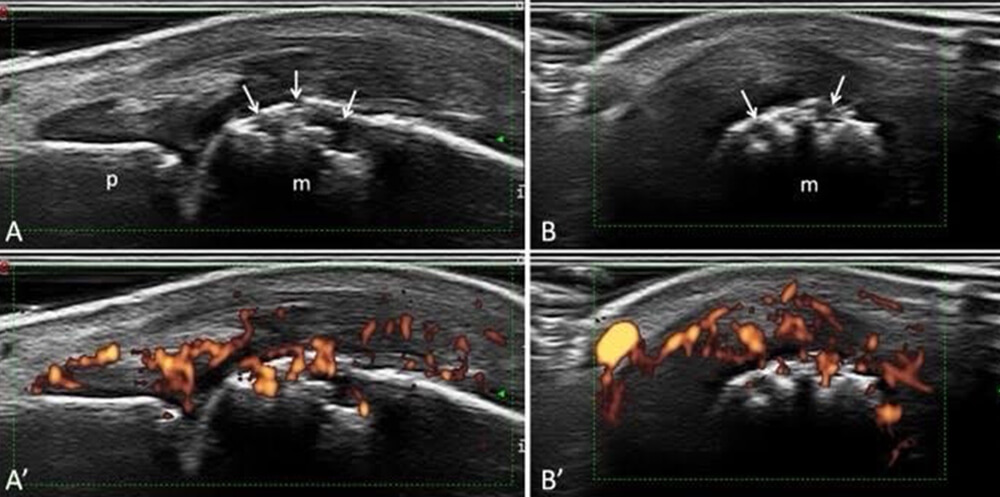

エコー:滑膜炎の評価を簡便にできるので、診断や治療評価に有効です。